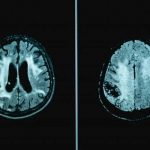

La hipertensión arterial y la diabetes podrían alterar la estructura del cerebro

En general, se cree que la presión arterial alta y la diabetes tipo 2 afectan al cuerpo, pero un nuevo artículo ha proporcionado evidencia...